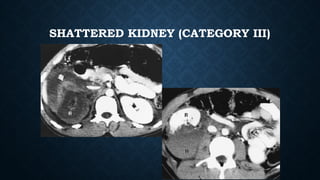

SHATTERED KIDNEY (CATEGORY III)